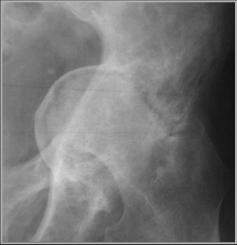

Paget’s Disease